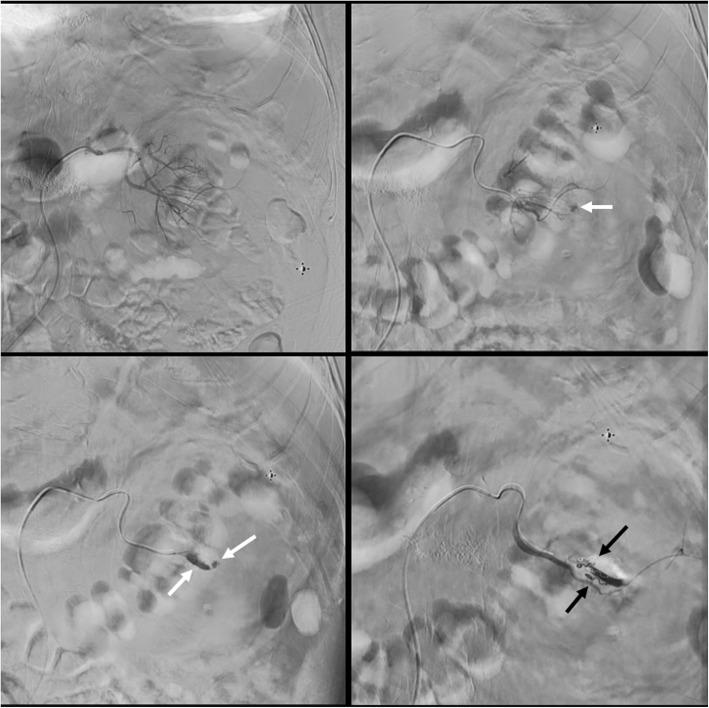

A 79 years old diabetic and hypertensive male with stage-4 chronic kidney disease who previously had left extracorporeal shockwave lithotripsy and FURS with Holmium laser lithotripsy, presented with bilateral large renal calculi. He underwent simultaneous bilateral FURS and Holmium laser lithotripsy and was discharged home the following day with almost clear urine. Four days post-discharge, he presented with gross hematuria for which he required hospitalization and blood transfusion. CT scan demonstrated left subcapsular, perinephric and retroperitoneal hematoma. Angiography showed contrast extravasation from pseudoaneurysms in two small branches of left renal artery. Both were selectively embolized with micro-coils and this led to the cessation of the hematuria.

一名79岁患有糖尿病和高血压的男性,处于4期慢性肾病,既往曾接受过左侧体外冲击波碎石术以及FURS联合钬激光碎石术,此次因双侧大型肾结石就诊。他接受了同期双侧FURS联合钬激光碎石术,术后第二天几乎尿液清澈时出院。出院后4天,他出现肉眼血尿,为此需要住院并输血。CT扫描显示左侧包膜下、肾周和腹膜后血肿。血管造影显示左肾动脉两个小分支的假性动脉瘤有造影剂外渗。两者均用微线圈进行了选择性栓塞,这使得血尿停止。